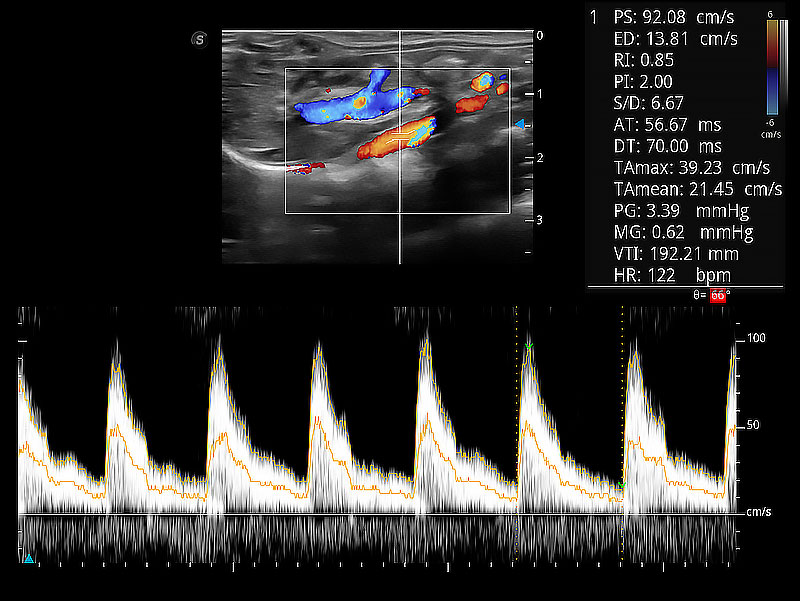

ProPet 80 配備了豐富的心臟探頭群、先進的成像技術(shù)和專業(yè)的心臟測量工具,可幫助動物醫(yī)生為不同體型和生理結(jié)構(gòu)的動物提供心臟和心肌功能的全面評估。

隨著取樣門位置改變,頻譜多普勒包絡可進行自動眼蹤測量,且可自由配置測量的參數(shù)。